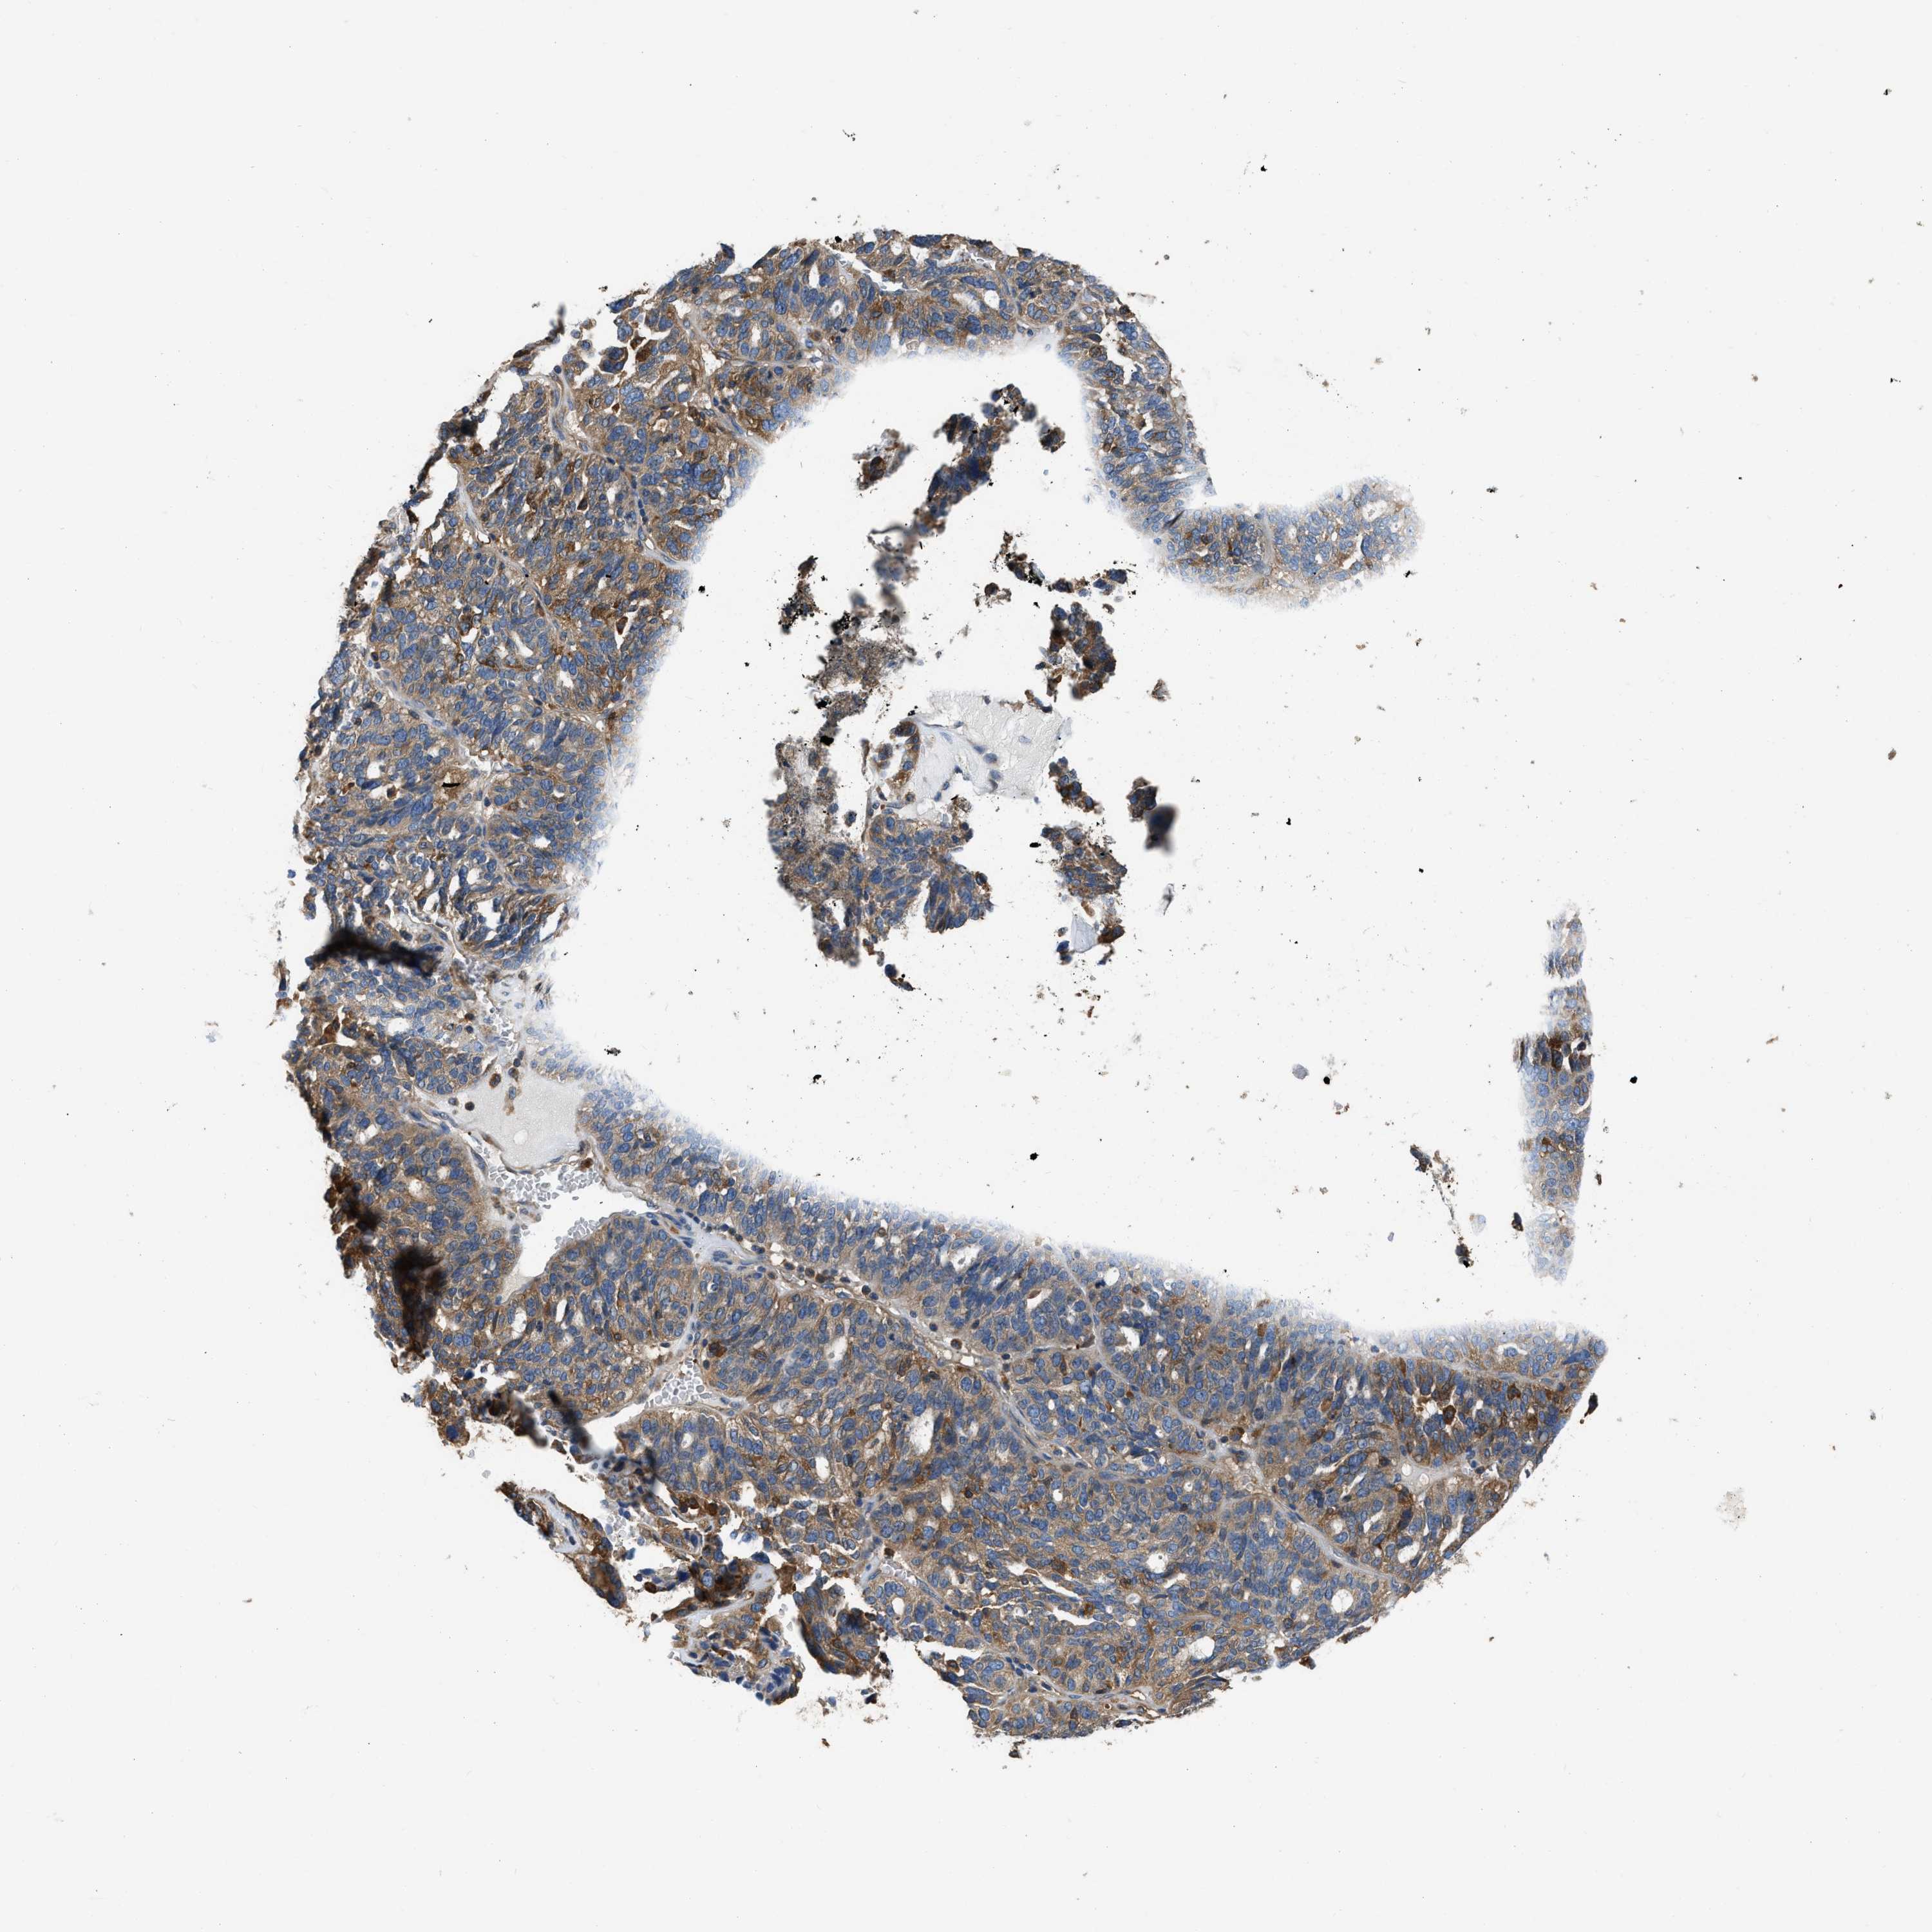

OVARIAN CANCER - Protein expressioni

A mouse-over function shows sample information and annotation data. Click on an image to view it in a full screen mode. Samples can be filtered based on level of antibody staining by selecting one or several of the following categories: high, medium, low and not detected. The assay and annotation is described here.

Note that samples used for immunohistochemistry by the Human Protein Atlas do not correspond to samples in the TCGA dataset.

Antibody stainingi

Antibody staining in the annotated cell types in the current human tissue is reported as not detected, low, medium, or high, based on conventional immunohistochemistry profiling in selected tissues. This score is based on the combination of the staining intensity and fraction of stained cells.

Each image is clickable and will lead to virtual microscopy that enables deeper exploration of all samples and also displays staining intensity scores, fraction scores and subcellular localization as well as patient and tissue information for each sample.

Antibody HPA029501

Antibody CAB019421

Cystadenocarcinoma, serous, NOS

Carcinoma, endometroid

Cystadenocarcinoma, mucinous, NOS

Carcinoma, NOS